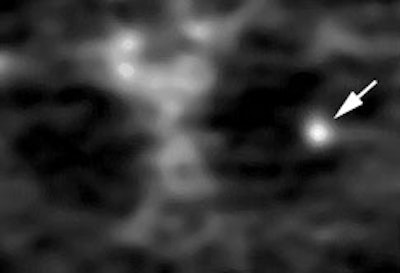

Lung cancer 1 cm lesion: The images below were from a patient with a 1 cm sized right upper lobe lung cancer. Note the excellent conspicuity of the lesion on FDG PET imaging. The exam was acquired using an ECAT EXACT PET scanner (CTI) with 5 min/bed emission and 2 min/bed segmented transmission. OS-EM iterative reconstruction was used for exam reconstruction. Case courtesy of Mallinckrodt Institute of Radiology/ Barnes Hospital, St. Louis and CTI PET Systems, Inc. |